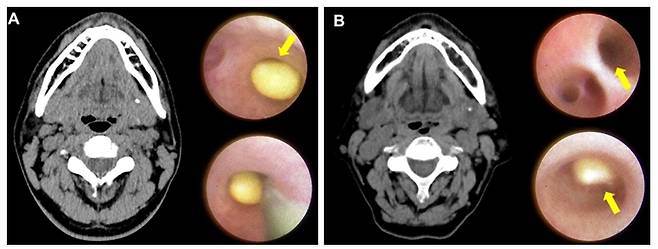

턱밑샘 타석증은 침샘에 결석이 생겨 침의 흐름을 방해하고 염증·통증을 유발하는 질환이다. 특히 턱밑샘 깊은 곳이나 혀 근육 아래 위치한 결석은 촉진이 어렵고 제거가 까다로워 치료법 선택이 중요하다.

기존에는 비내시경적 경구강 타석 제거술(Transoral Stone Removal, TOSR)이 주로 사용됐지만 드물게 부종, 통증, 혀 감각 마비 등의 합병증이 생길 가능성이 있었다. 내시경 보조 타석 제거술과 기존 경구강 타석 제거술의 임상적 유용성을 비교한 연구 역시 부족해 환자가 치료 수단을 결정하는 데에 어려움이 있었다.

임재열 교수 연구팀은 2017년부터 2024년까지 87명의 턱밑샘 타석증 환자를 대상으로 내시경 보조 타석 제거술(SASR)과 전통적 수술법(TOSR)을 비교했다. 그 결과, SASR 그룹(70명)의 타석 제거 성공률은 98.57%로 나타났으며, TOSR 그룹(17명)에서는 94.12%로 나타났다.

SASR 그룹의 합병증 발생률은 7.14%로, TOSR 그룹의 41.18%에 비해 현저히 낮으며, SASR을 받은 환자 중 72.09%가 수술 후 침샘 기능을 완전히 회복했다. 두 그룹 모두 연구기간 동안 타석 재발 사례는 없었다.

또 이번 연구에서는 내시경 보조 타석 제거술을 통해서 더 작은 크기의 더 깊은 곳에 있는 실질 내 타석들도 제거할 수 있다는 사실도 재확인했다.